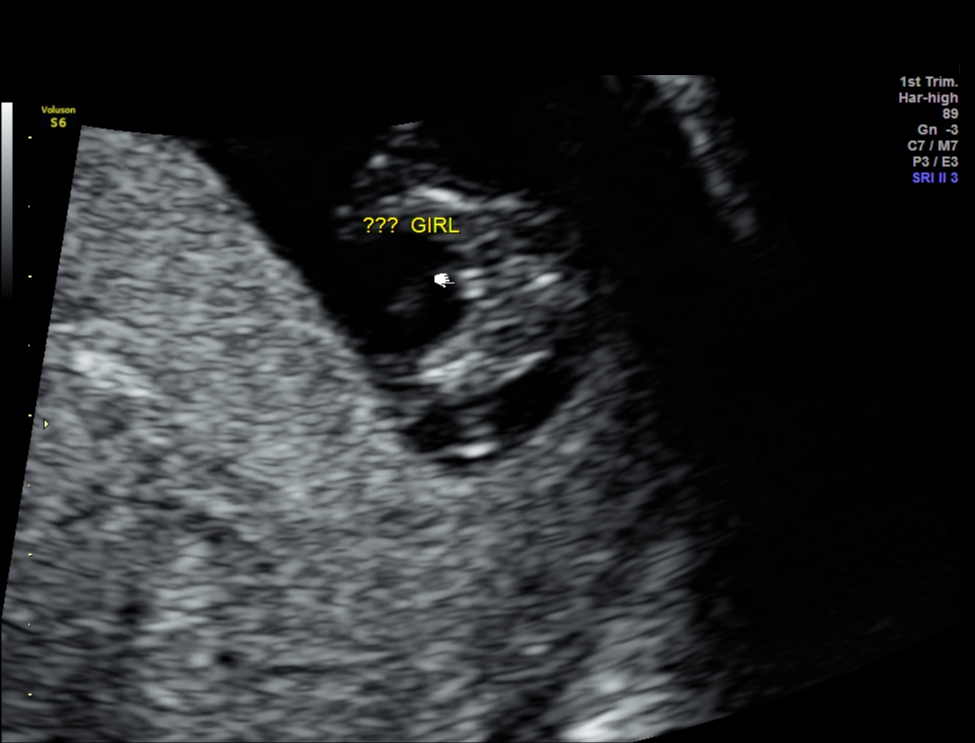

This is my second thread that I posted to ask about my baby's nub and hopefully someone will reply me this time :) I am not an expert in this area and i have been trying to look over hundreds of pictures and still confused about identifying nub correctly.

Can you see a nub in this pic and what is your guess? Very appreciated any help!!!